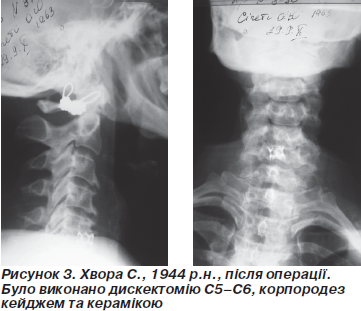

У неврологічному статусі були порушення чутливості в сегменті С5–С6, м’язова слабкість, хворі відмічали, що такий стан в них з’явився приблизно через один-два роки після лікування, вони лікувалися в неврологічному відділенні і відчували незначне покращення. Такі хворі потрапляли до нас на лікування, і ми проводили хворим функціональні рентгенограми й спіральну КТГ, де було виявлено нестабільність на рівні С5–С6.

Нами було проведено детальне обстеження, як рентгенологічне, так і КТГ, також МРТ, де було виявлено стеноз шийного каналу за рахунок остеофітів на рівні С5–С6 і протрузію диску на рівні С5–С6, склероз покривних пластин і нестабільність сегмента на рівні С5–С6, виділилися неврологічні симптоми, зниження рефлексів із руки, гіпостезія в зонах іннервації С5–С6.

У групи хворих (17), які протягом життя мали травму шиї, але за медичною допомогою не зверталися, не було виявлено клінічної симптоматики на час травми в 3 пацієнтів, у яких після проведеного консервативного лікування стан не покращився, а в 14 пацієнтів стан покращився і показань до хірургічного втручання не було. З цієї групи 3 хворим було проведено хірургічне втручання. Хочемо відмітити, що всім хворих, яким було проведено хірургічне втручання, нами був проведений передній доступ до грижі під контролем ЕОП. Здійснено вихід на нестабільність, проведено резекцію диска та покривних пластинок і вставлено кейдж того розміру, що нам було потрібно. Кейдж ми заповнювали кістковою стружкою, яку перемішували з гідроксилапатитною керамікою, а вздовж і зовні кейдж заповнювали гідрокситапатитною керамікою у вигляді півкуль. На нашу думку, таке заповнення кейджа дає добрий результат за рахунок виступів кейджа, які входять в губчасту частину тіла, а всередині кейджа кістка перемішана з гідроксилапатитною керамікою, що дає добрий результат у плані регенерації кістки.

При хірургічному втручанні, де було виявлено стеноз шийного каналу, нами був зроблений доступ той же, що і в попередніх хворих, але, крім видалення тіл хребцевого диска, нами було частково виконано резекцію тіла сегмента компресії хребців, вставлено кейдж і виконано його заповнення, яке не відрізнялося нічим від того, що виконано іншим пацієнтам.

Відмічаємо, що чим раніше буде виявлено нестабільність шийного відділу хребта, тим швидше настане ефект від лікування. На нашу думку тільки ретельно зібраний анамнез хворого дозволяє детально оглянути хворого, а неврологічний анамнез дає можливість чітко дообстежити хворого за допомогою комп’ютерної томографії й МРТ. Хірургічне втручання спрямоване на резекцію диска та стабілізацію нестабільного сегмента, бо без стабілізації переднього корпородезу стан хворих погіршиться. Передня стабілізація, на нашу думку, має вести до стабілізації і швидкої консолідації сегментів. При стенозі шийного каналу має бути чітко зроблена декомпресія і ревізія шийного каналу, і тільки після цього виконується корпородез.